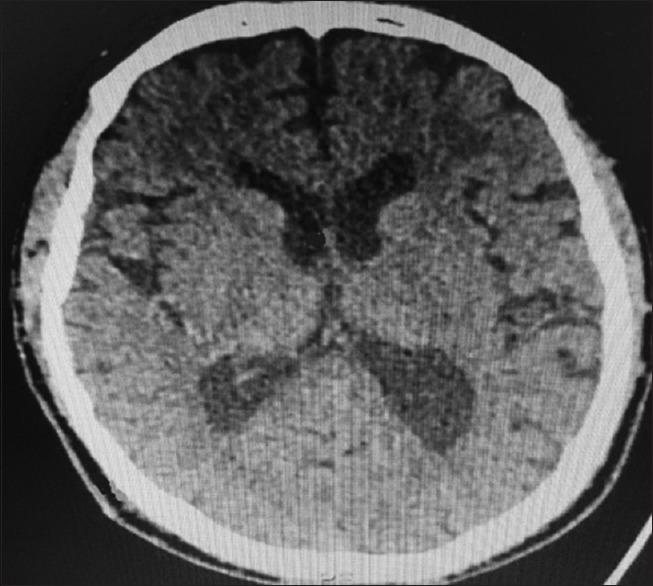

Ventriculoperitoneal (VP) shunt is a day-to-day procedure performed by a neurosurgeon. The most frequent associated complications are obstructive and infectious. Although rare, there are well-reported complications related to the poor positioning of the distal catheter, with perforation of organs and tissues. Still rarer are the complications related to the migration of this catheter.

We describe an atypical case of VP shunt postoperative by normal pressure hydrocephalus. After well-documented proper positioning of the distal catheter into the intraperitoneal cavity, it protruded into the subcutaneous space. Even on a new documented satisfactory abdominal tomography, this catheter migrated back again to the subcutaneous tissue.